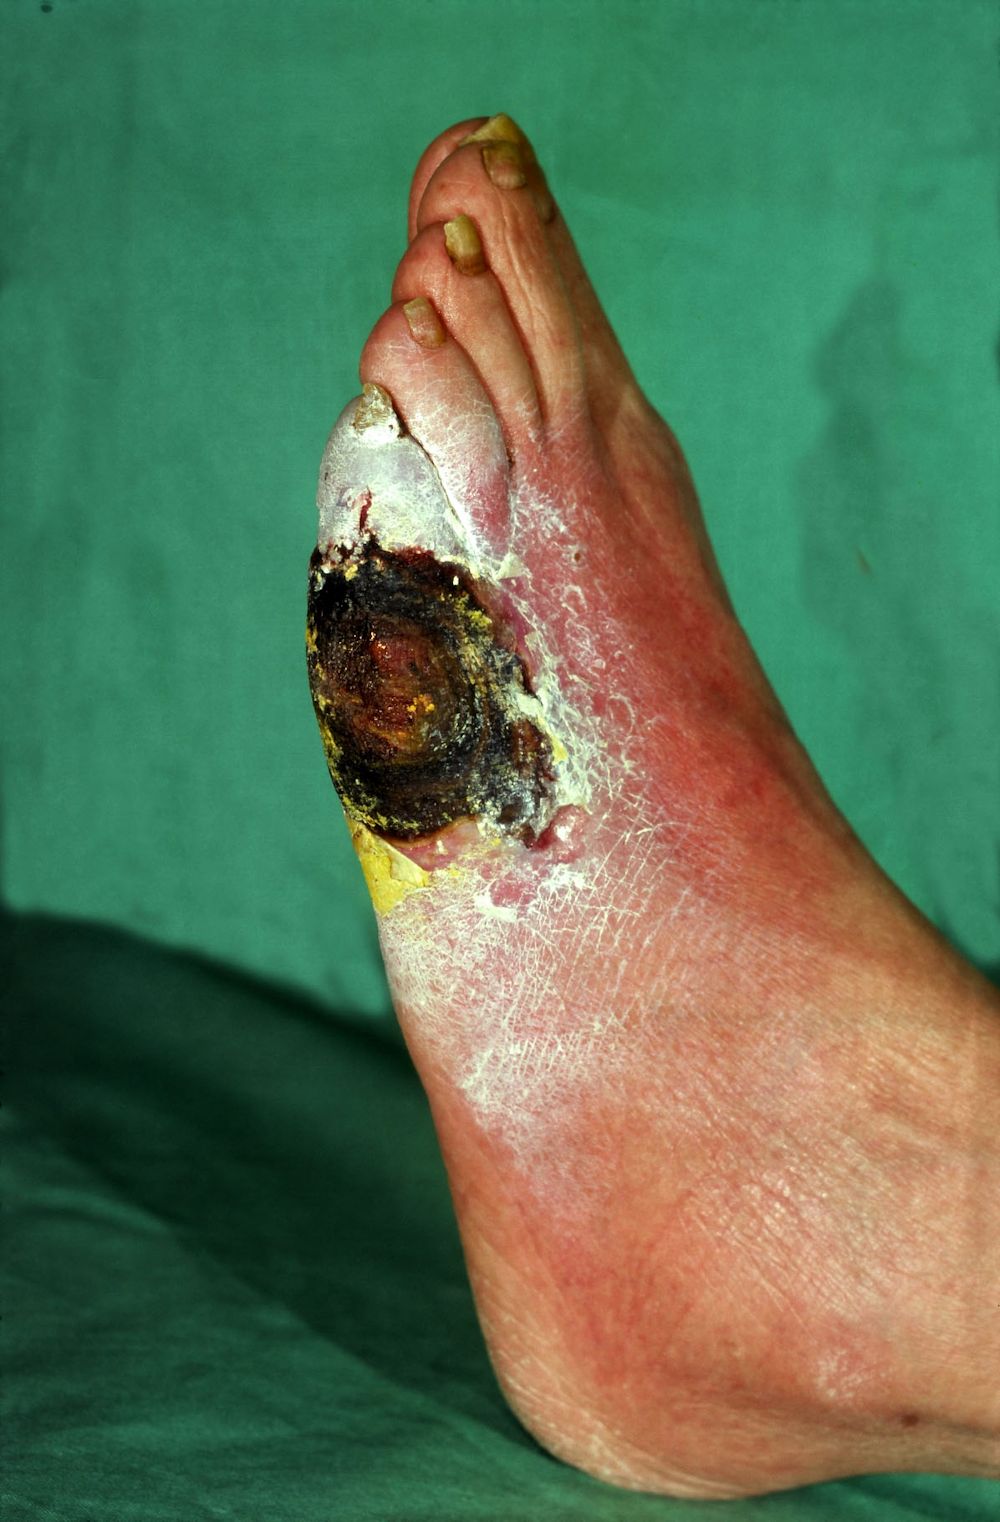

Diabetische voet

De

diabetische voet is een neuropathische voet op

basis van perifere neuropathie bij diabetes. Het is een complicatie van diabetes

waar ongeveer 15% van alle diabetes patiënten uiteindelijk mee te maken krijgt.

De problemen zijn identiek aan de neuropathische voet bij lepra. Bijkomend probleem

bij diabetes is een verhoogde gevoeligheid voor infectie, en dat de vaatvoorziening

ook gestoord kan zijn. De varianten die men kan aantreffen zijn:

- alleen

neuropathie (60-70%)

- alleen perifeer arterieel vaatlijden (15-20%)

-

neuropathie + perifeer arterieel vaatlijden (15-20%)

![Diabetische voet (click on photo to enlarge) [source: www.huidziekten.nl] Diabetische voet](../../../images/diabetische-voet-1z.jpg) |

| diabetische

voet |